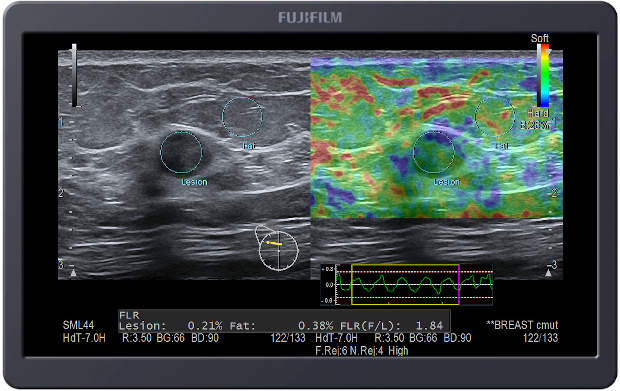

Elastografia tkankowa w czasie rzeczywistym (RTE)

Elastografia z pomiarem współczynnika odkształcenia stanowi łatwy sposób wykrywania i oceny zmian ogniskowych w piersiach i ma na celu zwiększenie wykrywalności raka piersi.

Elastografia wizualizuje sztywność tkanki w czasie rzeczywistym w postaci mapy kodowanej kolorem. Oprócz pomiaru jakościowego możemy dokonać pomiaru współczynnika odkształcenia. W przypadku badania piersi jest to stosunek odkształcenia tkanki tłuszczowej i zmiany, czyli Fat Lesion Ratio (FLR). Wyjątkowym ułatwieniem jest zautomatyzowany wybór obszaru zainteresowania – wystarczy zaznaczyć zmianę ogniskową, a system sam wykryje, i porówna ją do tkanki tłuszczowej.